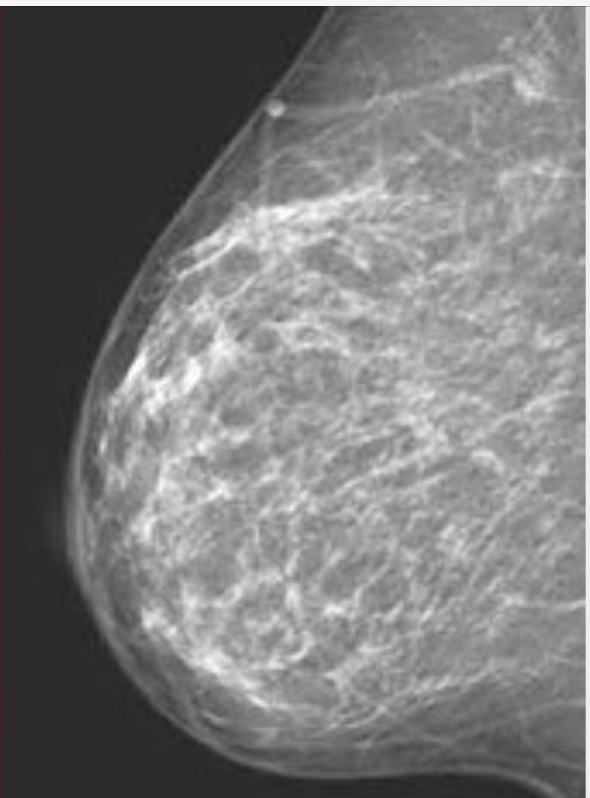

In my attempt to work through my “to do list” while Carter is off working at camp for the month I made a call to my radiologist to get my long overdue mammogram. To my surprise they had an opening this morning and I knew I should take it, even though I would have preferred to postpone it even longer. The scheduler asked me if I wanted a new 3D mammogram. I asked what the benefits were and then forgot to listen to the answer, while I day dreamed that a 3D would be a less smashing procedure.

If you are a man who is still reading let me describe what a regular mammogram is like. A strange woman takes your naked breast in her hand and lays it on a cold plastic plate and then spreads it out to be as flat as possible, then while still holding your breast she brings the clear plastic top plate down to sandwich your breast between the two plates with what my tech says is 20 lbs of pressure. You stand there, naked and in pain as she walks behind the machine to take the image while you are holding your breath so that your breasts don’t move. Move? The 20 lbs or pressure is holding me by the t$t. Repeat on the other breast and then again with them both at a 45 degree angle. Four major mashings.

My imagination immediately thought that a 3D mammogram would be something like a cup I just hung my breast into and it took pictures all around it while it just hung there. What was I thinking? That a woman might have invented the new technology?

For the record the 3D machine works exactly like the old machine as far as the smashing part goes, but costs $60 more. Now I’m sure the picture must be better and hopefully the quality of catching potential cancers is improved, but the customer experience is exactly the same.

That being said, I encourage all woman over 40 to go have your mammogram no matter how uncomfortable. I know that insurance companies have been fighting about how often they will pay for them, but don’t be deterred.

Now to all the women imaging engineers in the world, and I am sure there must be at least three of you, please consider inventing the machine my mind made up. Even if we have to lay on our stomach on a table with a hole in it with our breast hanging down to get a 3D image it would be better than smashing them. As it is my breasts already resemble two blue berry pancakes with one blue berry each and I can’t imagine the smashing is doing anything to help keep them perky.